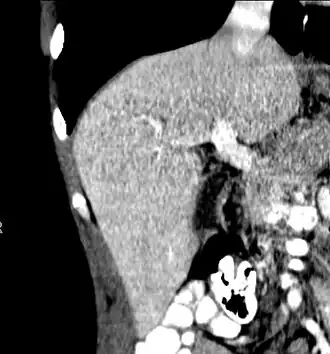

-

Axial CT image showing anomalous hepatic veins coursing on the liver's subcapsular anterior surface[74] -

Maximum intensity projection (MIP) CT image as viewed anteriorly showing the anomalous hepatic veins coursing on the anterior surface of the liver -

Lateral MIP view in the same patient as previous image -